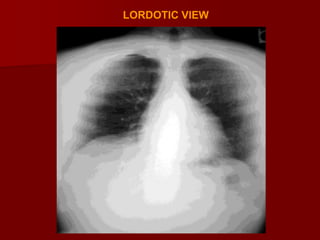

Angulation:

With the patient in a more lordotic projection and in

Apicogram the clavicles will project superiorly relative

to the upper thorax again causing some distortion of

the normal mediastinal anatomy.

With the lordotic projection of the ribs assume a

more horizontal orientation.

Occasionally a lordotic x ray can be obtained

intentionally to better visualize structures in the

thoracic apex obscured by overlying boney

structures.

LORDOTIC VIEW

It is particularly useful for lung apices

This view helps in conforming middle lobe and lingular

abnormalities

This view is also helpful in determining the anteropostero

location of a lesion